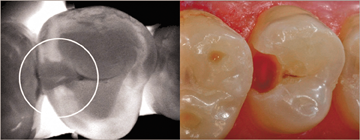

CariVu offers the clinician a precise picture of caries by using near infrared transillumination technology to give clinicians a view of carious lesions and cracks. Flexible “arms” on the end of the device tip straddle the tooth, and near infrared photons are emitted through the arms and travel from the root to the crown of the tooth. Dense enamel reflects the photons while porous lesions trap and absorb the photons.

As a result, healthy tooth appears light, and lesions appear dark, giving clinicians a structural view of the lesion whether it’s interproximal occlusal, or around restorations or a crack. As the old saying goes, “What you see is what you get,” or as DEXIS likes to say, “What you see is what is there.” CariVu technology has a very high detection accuracy -- an interproximal dentin caries detection rate of 99 percent. As a result, clinicians can obtain highly accurate diagnostic images in a noninvasive manner with absolutely no ionizing radiation.